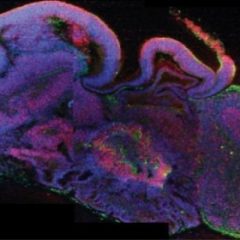

Cientistas criam cérebros através de células estaminais

O feito é da autoria do Instituto Molecular de Biotecnologia de Viena, capital austríaca, que objetiva compreender melhor o desenvolvimento do cérebro, problemas relacionados e tratamentos. Segundo relata o Expresso, estes cérebros organoides foram criados através de células tronco embrionárias ou células de pele adulta, colocadas em pequenas gotas de gel. Os órgãos, sem capacidade […]